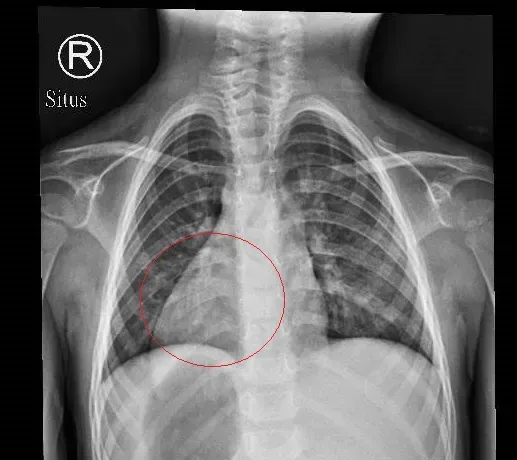

鏡面人

超音波

左右異位

完全性內臟異位